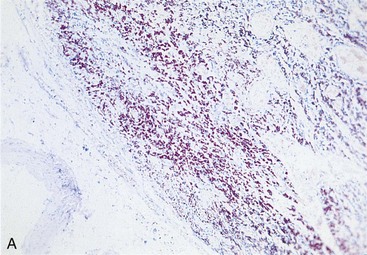

A new spectrum of disease developed in patients with acquired immunodeficiency syndrome (AIDS), making infection with M. avium complex the most common mycobacterial disease in these patients in the United States. In contrast to disease in other groups of patients, MAC infection in patients with AIDS is typically disseminated, with virtually no organ spared (Clinical Case 25-2). The magnitude of these infections is remarkable; the tissues of some patients are literally filled with the mycobacteria (Figure 25-8), and there are hundreds to thousands of bacteria per milliliter of blood. Overwhelming disseminated infections with M. avium are particularly common in patients who are in the terminal stages of their immune disorder, when their CD4 T-lymphocyte counts fall to less than 10 cells/mm3. Fortunately, with more effective antiretroviral therapy and the routine use of prophylactic antibiotics, M. avium disease infections in HIV-infected patients have become much less common. Although some patients with AIDS develop M. avium disease after pulmonary exposure (e.g., infectious aerosols of contaminated water), most infections are believed to develop after ingestion of the bacteria. Person-to-person transmission has not been demonstrated. After exposure to the mycobacteria, replication is initiated in localized lymph nodes followed by systemic spread. The clinical manifestations of disease are not observed until the mass of replicating bacteria impairs normal organ function.

image image

Figure 25-8 Tissue from a patient with acquired immunodeficiency syndrome who is infected with Mycobacterium avium complex, photographed under low (A) and high (B) magnification.